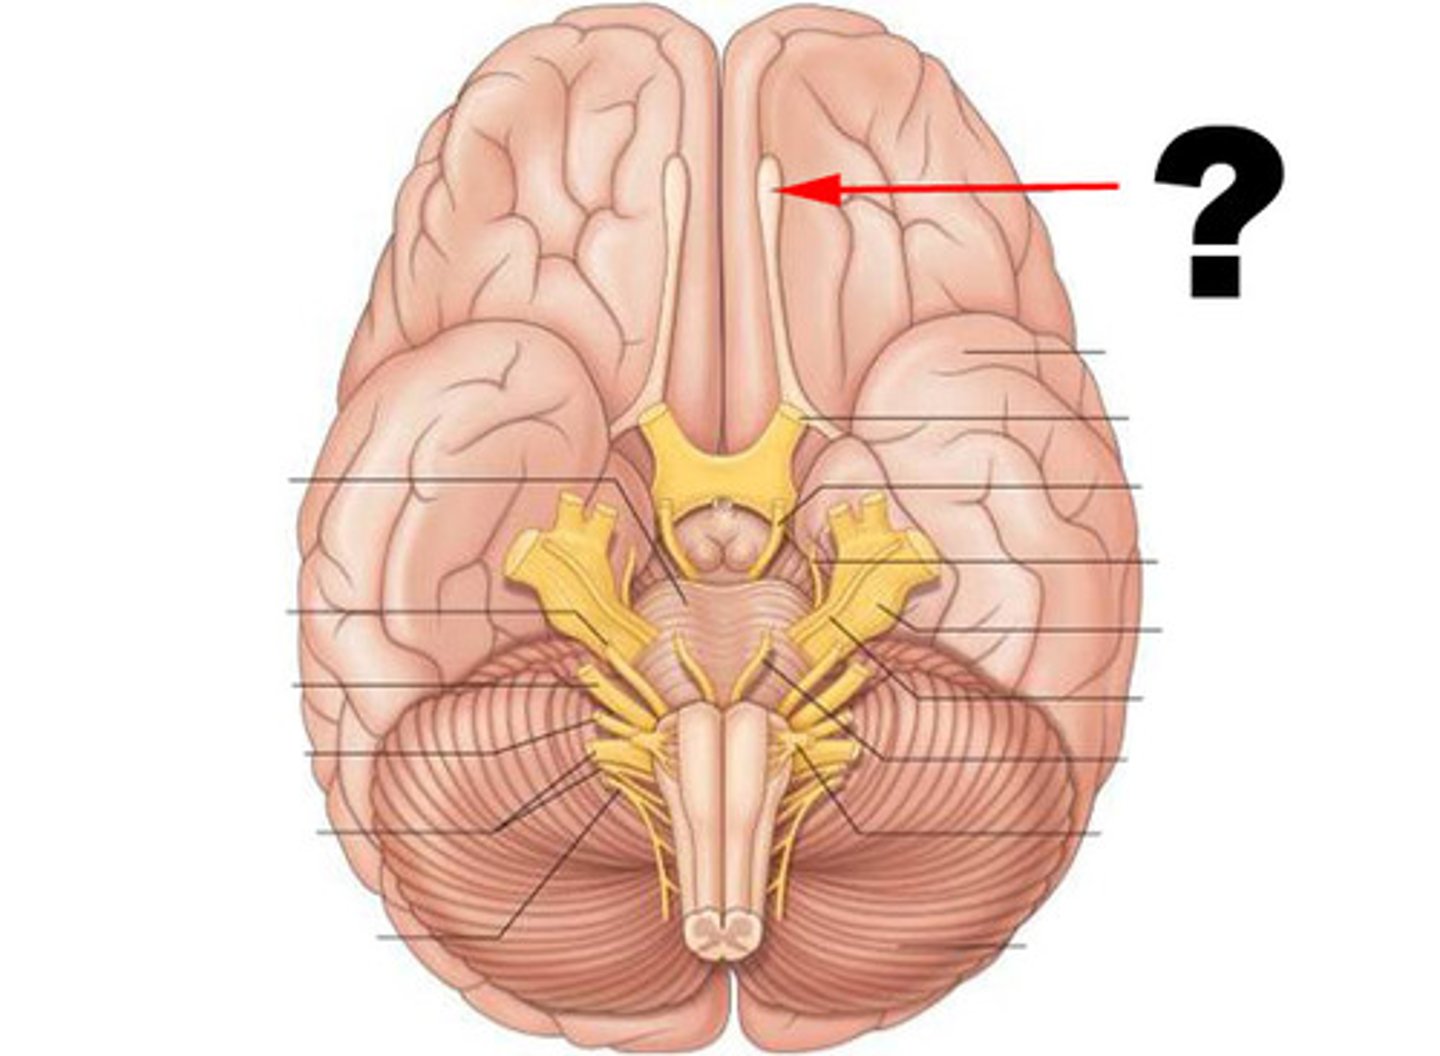

CN I: Olfactory Nerve

The first and shortest cranial nerve. It is a special visceral afferent nerve, which transmits information relating to smell.

Olfactory Bulbs

Lies in the olfactory groove within the anterior cranial fossa